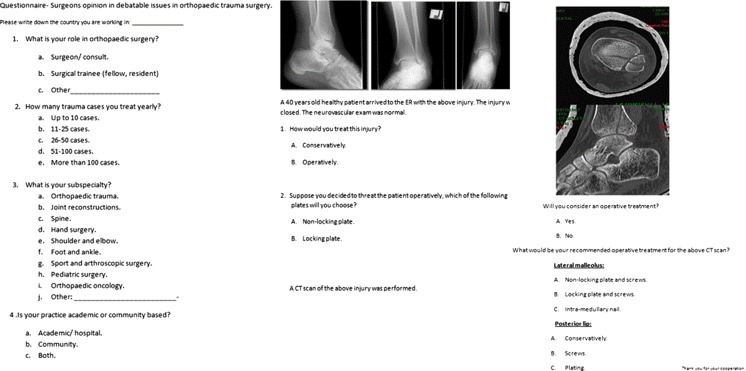

Fig. 1.

Study questionnaire